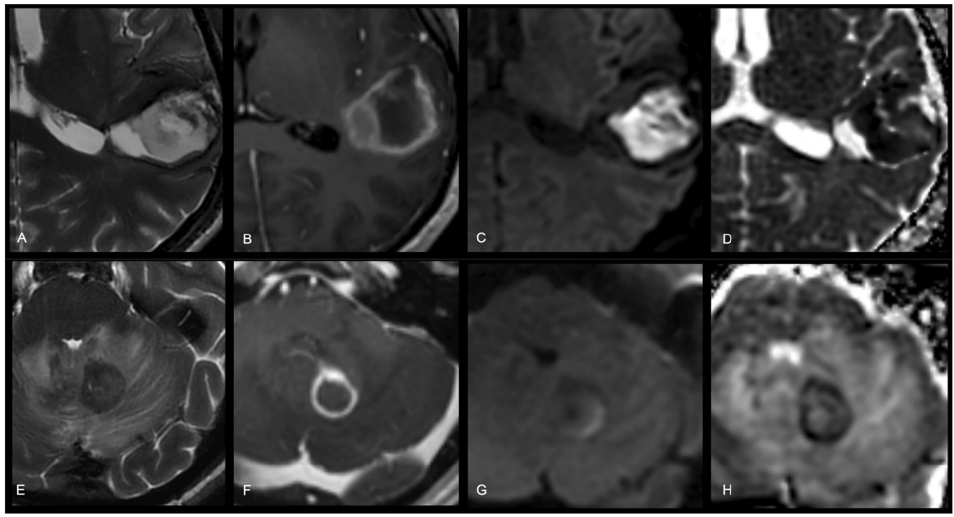

本综述由欧洲磁共振医学与生物学学会(ESMRMB)专家团队撰写,系统阐述了扩散加权成像(DWI)的技术原理、临床应用与标准化实践。文章重点推荐了单次激发回波平面成像(EPI)序列参数优化方案(如TR≥4500 ms、b值范围0-1000 s/mm2),强调了表观扩散系数(ADC)图与原始DWI联合解读的重要性,并详细解析了T2穿透效应、几何畸变等常见伪影的应对策略。该指南为提升DWI在神经系统疾病(如急性脑缺血)和肿瘤(如前列腺癌、乳腺癌)诊断中的准确性与可重复性提供了权威实践框架。